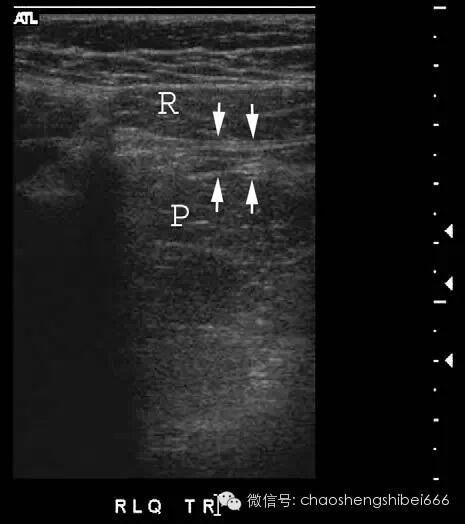

Puylaert在1986年首次提出超声探头逐级加压的方法诊断阑尾炎。如前所述使用线阵探头,逐步缓慢的加压以提高病人的耐受性。检查最好以问病人“你哪儿痛?”开始(而不是让病人指出疼痛的具体点)。无并发症的阑尾炎患者通常会指出疼痛具体位置。根据其指出的方位即是扫查的起始位置。患者指出疼痛部位的深方,常常会令人吃惊的发现病变阑尾。如果没有当即找到阑尾,就要对右下腹及盆腔进行全面系统的扫查,并且分别在横切面及纵切面摆动探头仔细扫描。经验不足的超声工作者经常因为没有足够的探头加压扫描而造成漏诊。足够的压力可以使后腹壁、腰大肌及髂血管显示(图1)。在Puylaert的文章中,插图清晰的反映了所需加压程度。

图1 15岁右下腹痛女孩的超声图像。后腹壁包括腰大肌(P)的显示表明加压充分。箭头表示前腹壁的腹直肌(R)与后腹壁的腰大肌之间被压的距离很小。